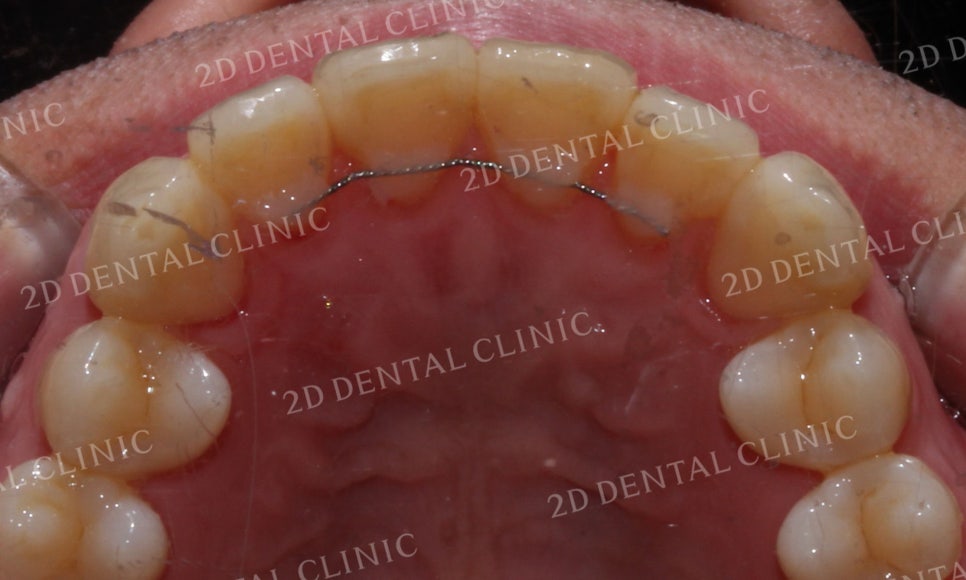

상악의 설측면을 보시면

전치부 치아의 총생을

확실하게 확인할 수 있는데요,

21번 치아가 회전되어 있어

전치부 치열을 더 삐뚤게 만드는 모습입니다.

21번 치아에서 발견되었던

치아의 회전이 가지런하게 바뀐 모습입니다.

또한 삐뚤삐뚤하던 전치부 치열도

부드러운 곡선 형태로 고르게

교정된 것을 확인할 수 있습니다.